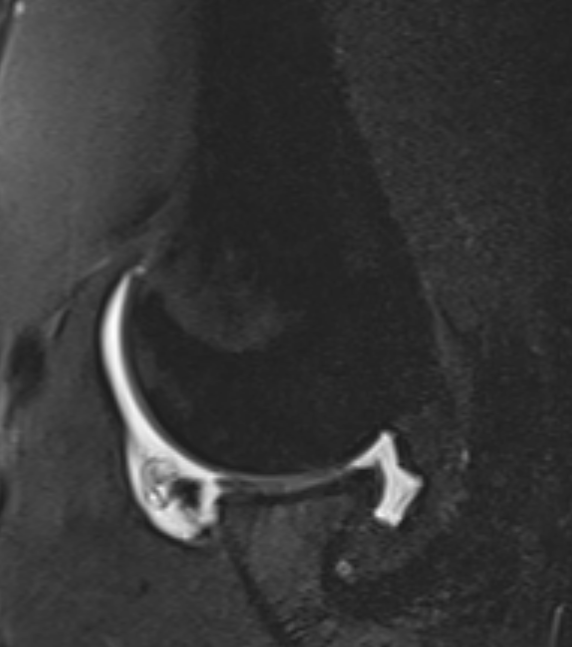

Anterior labral tear on ABER view